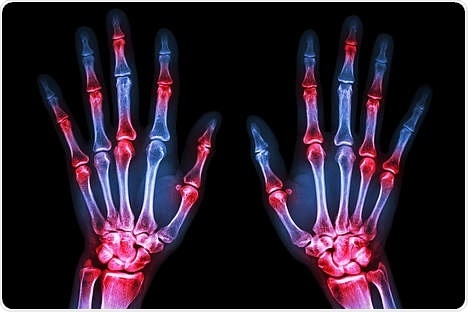

Rheumatoid arthritis is a common inflammatory joint disease. A feature of this disease is the increased fusion of endogenous immune cells (macrophages) to form so-called osteoclasts, which attack and break down bone tissue.

Just like other multinuclear giant cells, osteoclasts require enhanced energy metabolism for bone breakdown. The findings of this study now demonstrate that increases in osteoclast metabolism cannot be achieved in the absence of arginine.

The group led by Gernot Schabbauer from MedUni Vienna, who is head of the Christian Doppler Laboratory for Arginine Metabolism, has now shown in various animal models that systemically depleting arginine in the body slows down the metabolism of these giant cells, significantly diminishing their function. To achieve this, the researchers utilized the enzyme arginase, which lowers whole-body arginine levels. This resulted in decreased osteoclasts numbers in the bone, therefore leading to less disease instigated damage.